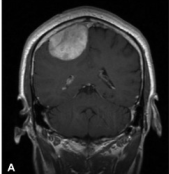

What's the Diagnosis?

Guess 1 / 5